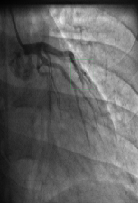

Marijuana Induced Coronary Vasospasm

Syed Iftikhar, Asma Jamil, Javad Savoj, Rajesh Gulati*